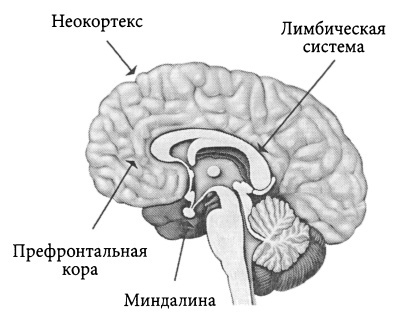

Как показывают исследования, за нашу самоидентификацию отвечает лишь некоторая часть нашей нервной системы. Она включает в себя как «древние» структуры, которая достались нам от более примитивных существ живших сотни миллионов лет назад (и формирующие в них некое единство всего организма) так и «новые» отделы коры мозга, ответственные за индивидуальный (а не видовой) опыт, наше «Я» и «сознательное» отношение к миру.

Большая же часть нервной системы человека «обслуживает» другие функции нашего тела, такие как: регуляция внутренних органов (сердца, легких, желудка и кишечника), обработку сенсорной информации от органов чувств (зрения, слуха, обоняния, вкуса и осязания), координацию и выполнение различных движений, поддержание гомеостаза — стабильного внутреннего состояния организма, температуру тела, баланс жидкостей, электролитов, а также другие параметры. И для определения личностных параметров эти функции не столь важны.

Обозначим части нервной системы, играющие в самоидентификации человека основную роль:

1) Ретикулярная формация – это сложная сеть нейронов, расположенная в центральной части ствола мозга (довольно маленькая по сравнению с большими полушариями или мозжечком). Считается одной из наиболее древних его частей, так как появилась на ранних этапах эволюции мозга. Критически важна в регуляции основных жизненно важных функций, таких как дыхание, сердцебиение, поддержание состояния бодрствования и перехода между сном и бодрствованием. Действует как фильтр для сенсорных сигналов, препятствуя перегрузке мозга информацией и может регулировать передачу болевых сигналов к мозгу.

2) Лимбическая система – также является одной из самых старых частей мозга, хотя и более «новая» по сравнению с ретикулярной формацией с точки зрения эволюционной истории, так как связана с более сложными социальными взаимодействиями и когнитивными способностями. Тоже занимает небольшую часть общего объема мозга. Хорошо развита у млекопитающих, где она участвует в процессах обучения, памяти и эмоционального поведения. Напрямую влияет на такие черты личности, как эмоциональная стабильность, реакция на стресс и взаимоотношения с другими людьми. Помогает усиливать воспоминания на основе эмоциональной значимости, регулирует гормоны, которые влияют на настроение и эмоции, играет ключевую роль в формировании новых воспоминаний и обучения, важна для пространственной памяти и переноса информации в долговременную память.

3) Префронтальная кора – составляет около 10% объема всего головного мозга и является специализированной областью внутри структуры неокортекса. Ответственна за регулирование сложных когнитивных процессов, включая планирование и принятие решений, социальное взаимодействие и самоконтроль. Связана с чертами личности, такими как ответственность, импульсивность и адаптивность. Участвует в удержание и манипулирование информацией в коротком временном промежутке для выполнения когнитивных задач.

4) Теменные доли – занимают около 5% объема головного мозга и также являются частью неокортекса. Важны в ориентации в пространстве, обработке сенсорных сигналов и интеграции информации для восприятия и понимания окружающего мира. Это может влиять на такие аспекты личности, как открытость к новому опыту и способность к адаптации. Помогает управлять вниманием и участвует в хранении семантической памяти.

5) Височные доли – часть неокортекса ответственная за обработку слуховой информации, понимание языка, визуализацию и восприятие эмоций, формирование воспоминаний.

6) Мозжечок – составляет около 10% от объема головного мозга, но содержит более 50% всех нейронов из-за его плотно упакованной структуры. Традиционно считается, что мозжечок участвует в координации движений, однако недавние исследования показывают, что он также может влиять на когнитивные функции и эмоциональную регуляцию, формирование процедурной памяти, такой как навыки и привычки (совместно с базальными ганглиями).